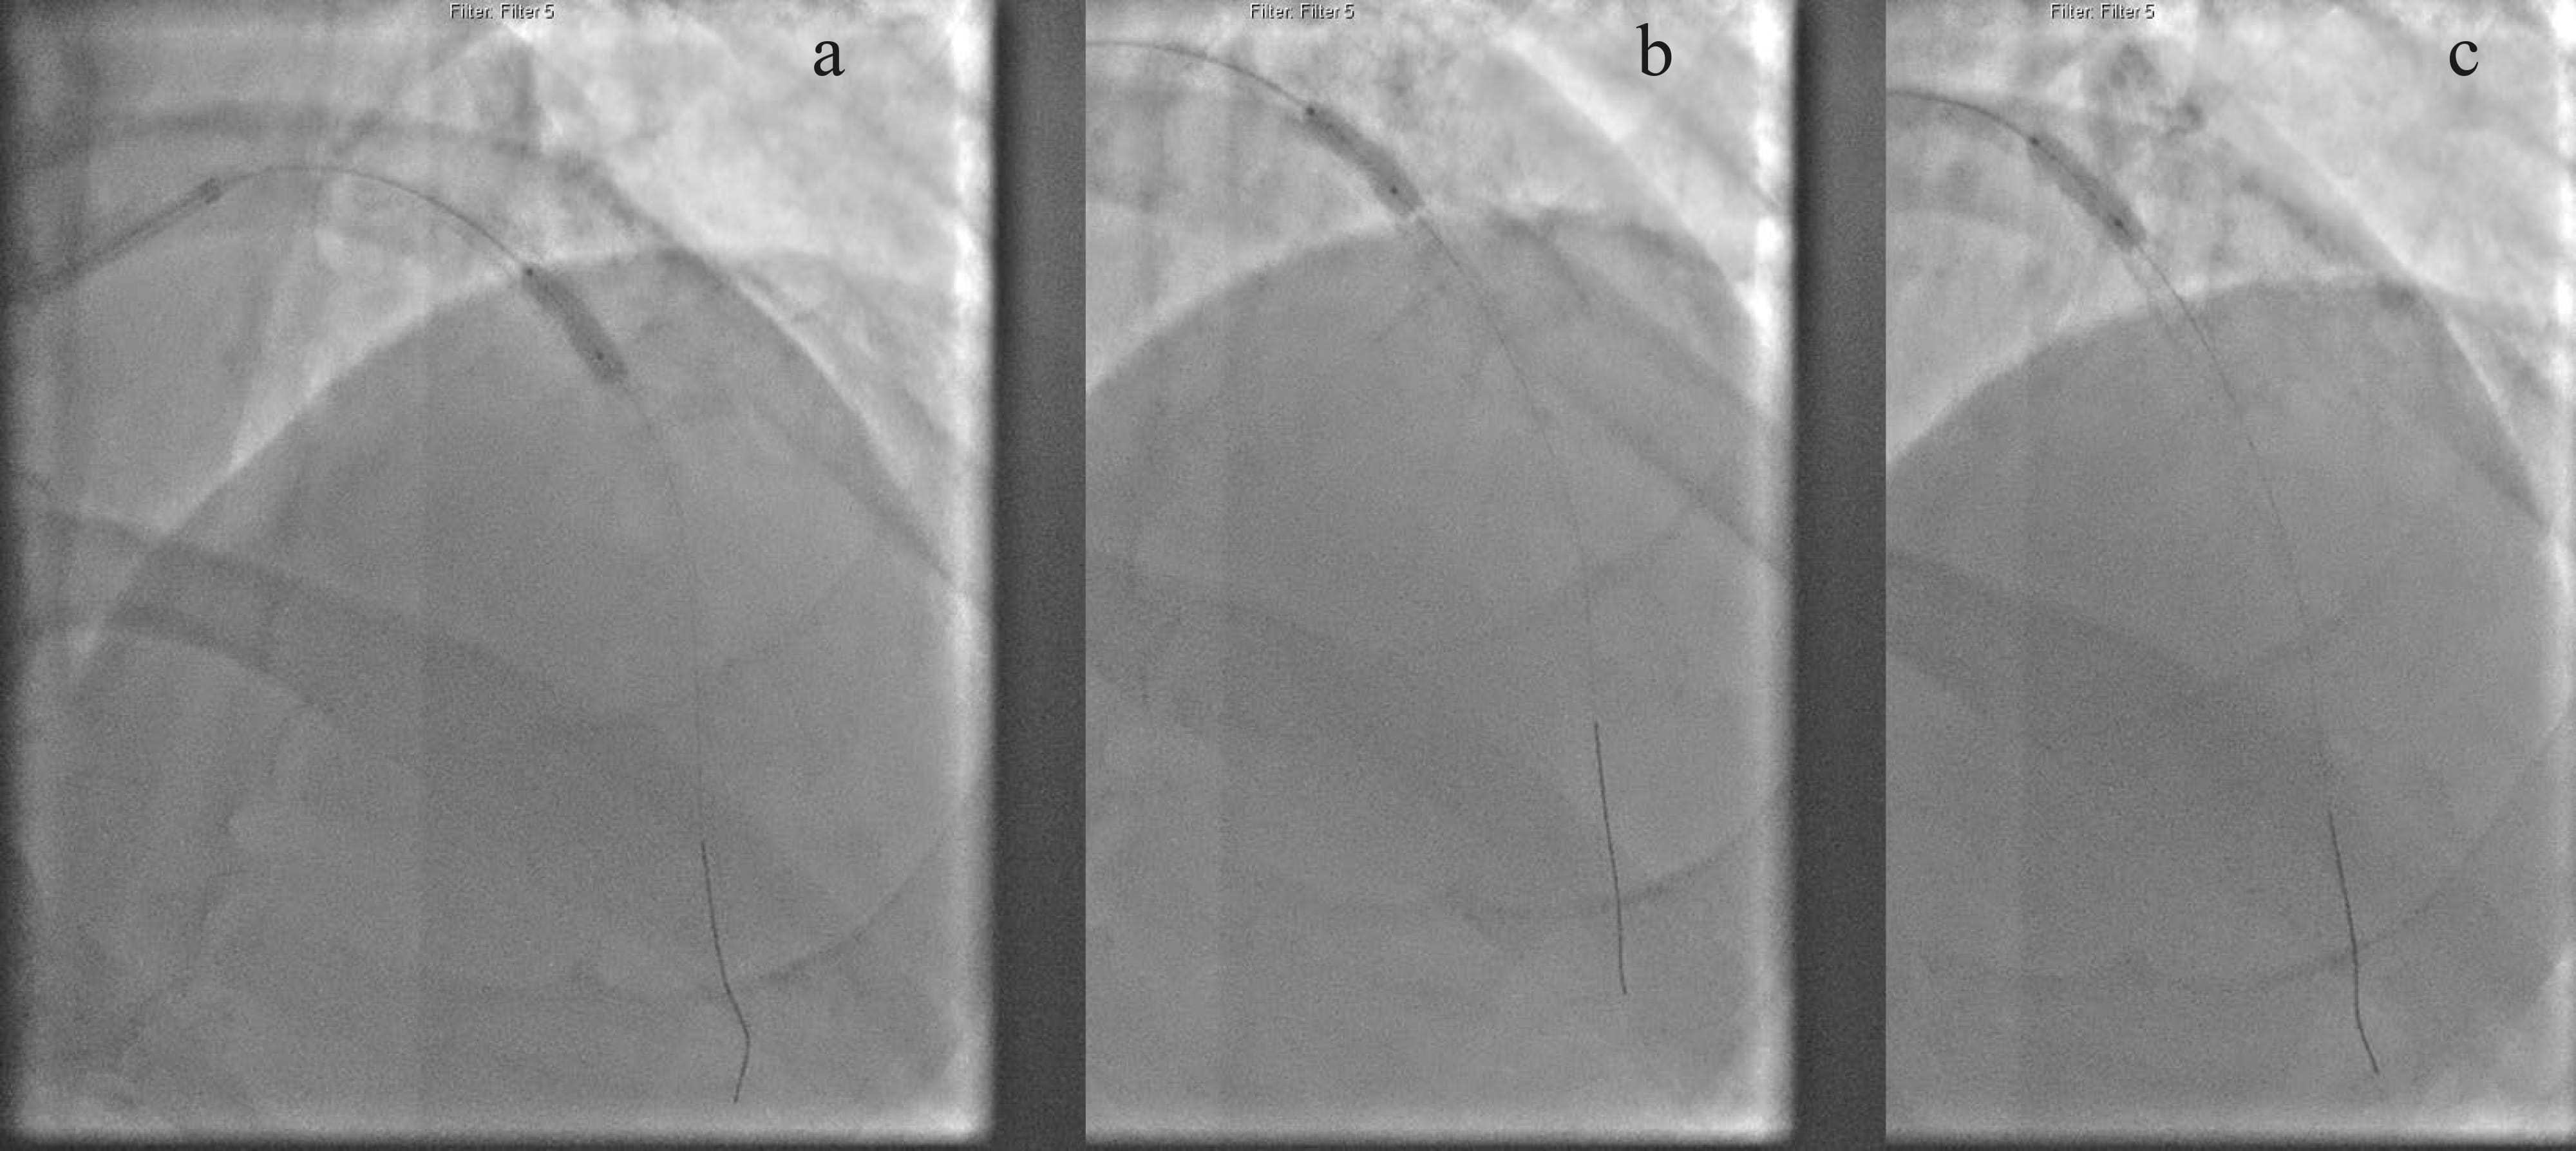

imaging visualised concentric calcium (Fig. 4). Subsequently, we used a 3.5 mm

intra-vascular lithotripsy (IVL) balloon (Fig. 5), which fractured the calcium

Fig. 4.3.5 mm intra-vascular lithotripsy successfully cracked the lesion. (a) 3.5 mm IVL balloon successfully inflated in the mid-segment. (b) IVL balloon expanding in the proximal segment. (c) IVL balloon fully expanded in the proximal segment.